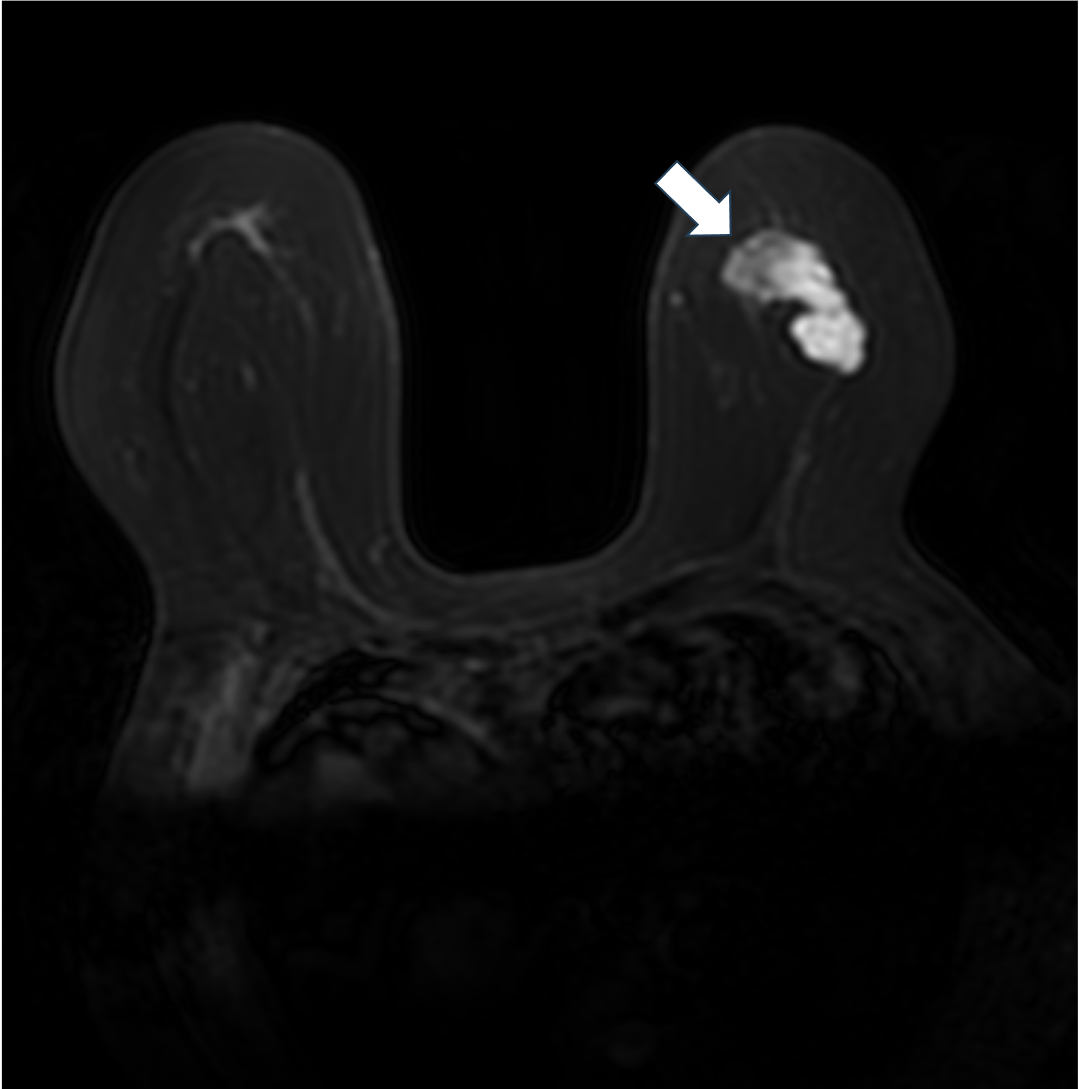

3. 拡散強調画像 b=1000(s/mm2)(造影前)

拡散強調像では腫瘤の乳頭側が高信号を示すが、それ以外の部分は周囲の乳腺組織と同等の信号を示す。乳頭側に細胞密度の高い腫瘍の存在が示唆される。